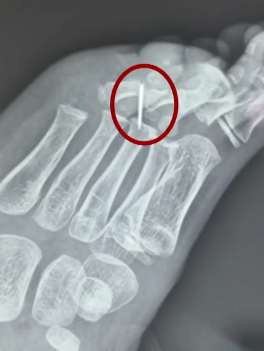

6岁男孩脚掌扎入1cm断针 医生用4小时才取出